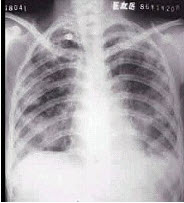

3、单项选择题

患者输液过程中突发胸闷,气急,咳痰,胸部正侧位片如图,最可能的诊断为()

A.硅沉着病合并感染

B.中央型肺水肿

C.真菌感染

D.间质性肺水肿

E.腺病毒肺炎